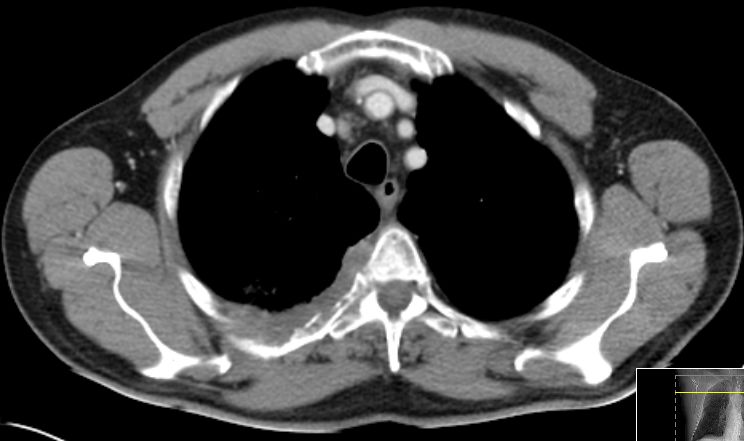

CT Infiltration des oberen Mediastinums. Flottierender Thrombus in der Vena cava superior.